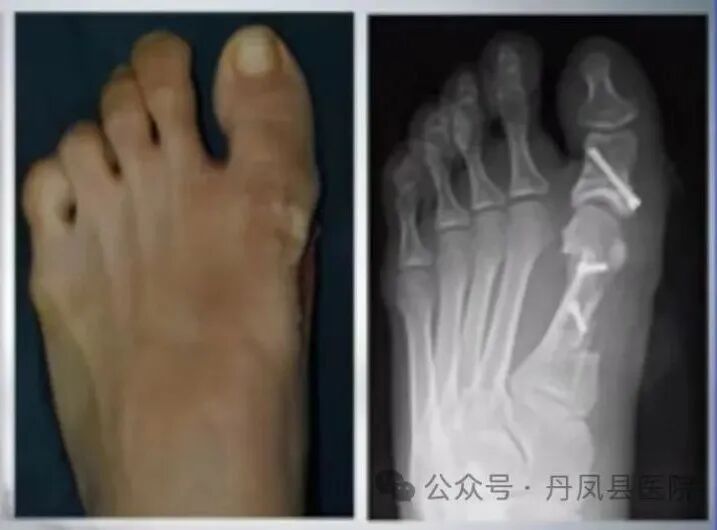

病例二:患者张某,女,42岁,左足拇外翻畸形3年余,行走疼痛,已严重影响到日常生活,经多方打听,来到我院骨一科就诊。收治入院后,骨一科主任李静宏带领科室团队为其进行了全面的足部检查,充分评估病情,研究手术治疗方案,最终成功为患者实施了拇外翻矫形术。术后患者恢复良好,并不停的称赞:“丹凤县医院医生的技术太好了,使我摆脱了多年来“大脚骨”的烦恼。”

![]()

图为患者术后足部图片